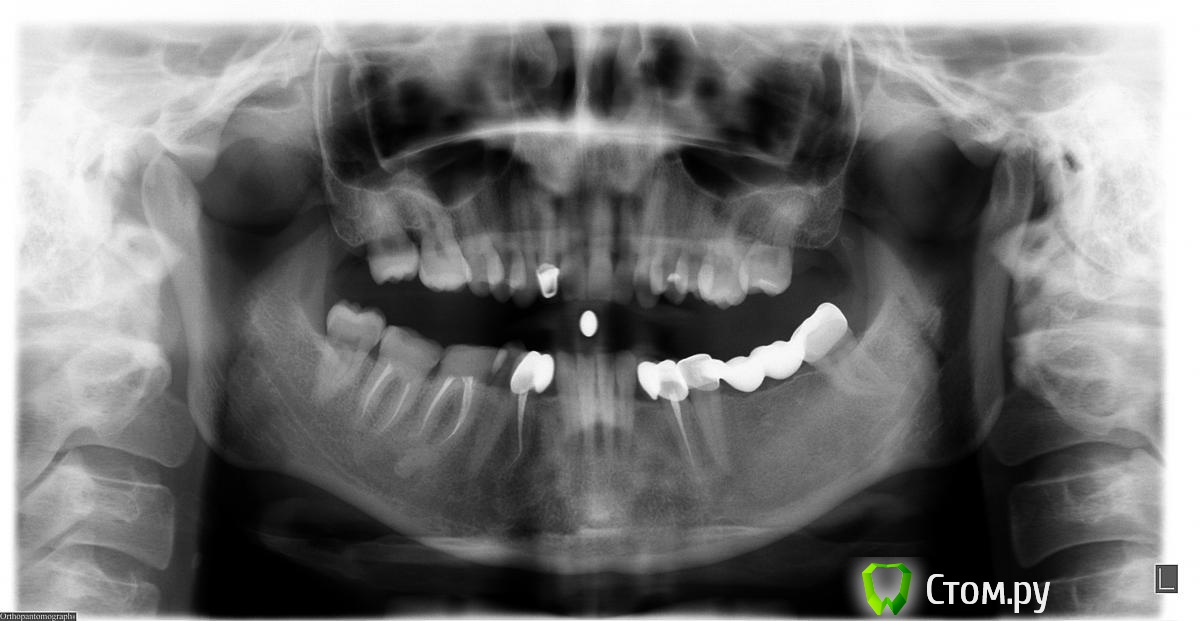

Эндж Опубликовано 30 июля, 2014 Поделиться Опубликовано 30 июля, 2014 Здравствуйте! Прокомментируйте, пожалуйста состояние моих зубов. Сейчас после ортодонтии и имплантации ношу пока времянки, через неделю планируется установка постоянных. Я вижу на двойке сверху гранулемуи мне кажется, что она увеличилась. Мой ортопед говорит, что канал хорошо пролечен и лучше не трогать, а я переживаю, что после установки постоянной коронки может начаться какая-нибудь проблема.Канал перелечили два с половиной года назад. Снимки:1) до перелечивания2) год назад3) и 4) вчера Ссылка на комментарий

M@estro Опубликовано 1 августа, 2014 Поделиться Опубликовано 1 августа, 2014 Я бы повторно в каналы не лез(если всё было сделано по современному протоколу- консервативное лечение вряд ли даст результат),а обратился бы к высококвалифицированному Врачу , который сможет выполнить операцию резекции верхушки корня. Ссылка на комментарий

red_butler Опубликовано 5 августа, 2014 Поделиться Опубликовано 5 августа, 2014 Коффедарма точно не было, а про запах хлорки не помню. А по снимку не видно качественно пролечен или нет?по снимку нормально пролечен. Соглашусь с M@estro -делать резекцию апекса Ссылка на комментарий